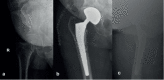

Methods: From March 2015 to March 2020, 138 patients were treated with Dualis Cup (Gruppo Bioimpianti-Peschiera Borromeo, MI, Italy) for a total of 141 implants (three cases were bilateral). The average age at the time of the surgery was 77. Patients' clinical and X-ray follow-up was at 1, 3, 6, 12 months and then once a year.

Results: Seven patients (4.9%) had complications which required a second surgery, but only one case (0.7%) of intraprosthetic dislocation (which required cup revision), was directly ascribable to the DM cup.

Conclusions: Improvements in design and materials of the third generation DM cups allowed both to reduce the rate of dislocations in high-risk patients (i.e., patients with neuro-muscular diseases and cognitive disorders, patients needing revisions, osteosynthesis failures, femoral neck fractures) and to achieve a survival rate similar to standard cups, ensuring a range of motion (ROM) very close to the physiological one. In our brief experience, Dualis Cups showed results comparable to those reported in the literature for Dual Mobility. If this data is confirmed by long-term studies, the use of DM cups could be extended even for young patients with high functional demands. (www.actabiomedica.it).